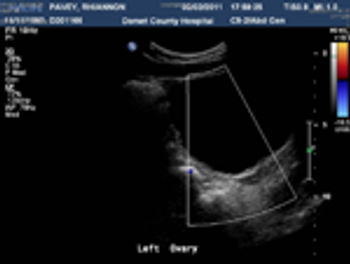

afe abdominal entry and prevention of retroperitoneal vascular injuries during laparoscopic surgery are the ultimate goals of any laparoscopic surgeon. Dr. Linda Nicoll and colleagues very capably have been able to describe a new technique and technology that prevent almost all retroperitoneal vascular injuries during laparoscopic entry.